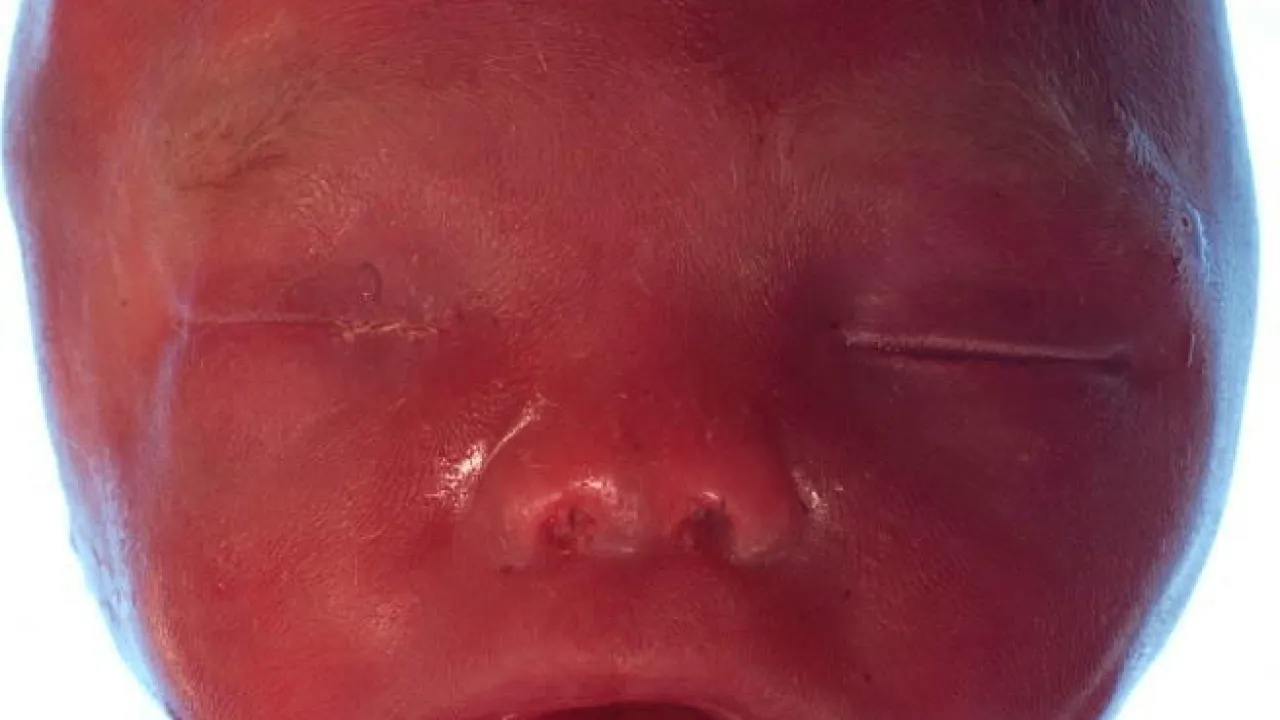

Cranium, Twin reversed arterial profusion sequence

Foot, Twin reversed arterial profusion sequence

Skeleton and body morphology, Twin reversed arterial profusion sequence